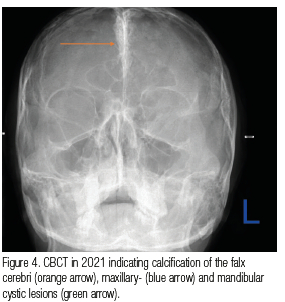

An 18-year-old male patient presented at our dental clinic in 2009 for a dental assessment. A panoramic radiograph was taken to evaluate dental crowning (Figure 1). An incidental finding was noted in the right maxilla, presenting as a well-demarcated, round, unilocular, radiolucent lesion with a corticated rim extending from the right maxillary tuberosity area to distal of the 16 causing impaction of the 18. A biopsy was taken and diagnosed as an odontogenic keratocyst (OKC) that was subsequently enucleated. In 2021 the patient returned and another panoramic radiograph (Figure 2) and a Waters view was taken where calcification of the falx cerebri was seen (Figure 3). On the panoramic radiograph an additional mandibular lesion was visible that presented as a well-demarcated, round, unilocular, radiolucent lesion with a corticated rim extending from distal of the 46 into the missing 47, 48 area. A CBCT was then taken to further analyse the lesions (Figure 4). A biopsy was taken in the right posterior mandible and diagnosed as an OKC. In 2023 the patient returned and a CBCT was taken. The right maxilla showed increased bone density adjacent to the enucleated lesion (Figure 5).

A diagnosis of Nevoid Basal Cell Carcinoma Syndrome (NBCCS) was made due to the multiple OKCs and calcification of the falx cerebri.